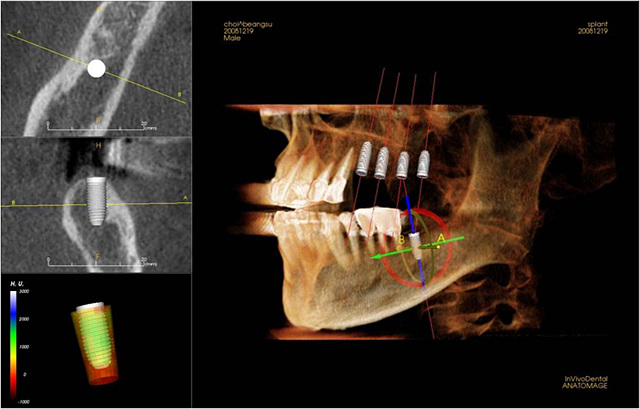

2. 디지털 장비의 정확한 분석

정확한 진단과 분석은 치료의 기본입니다. 3D CT 와 3D 보철 스캐너를 통해 정확한 진단과 계획이 가능합니다.

3. 철저한 계획과 가이드

환자분의 이해를 돕기 위해서는 물론이며, 치료의 정확성과 신속성을 위해 사전에 치료 계획을 수립하여 모의수술을 진행하고 수술용 가이드를 제작하여 정확한 위치와 최소한의 수술로 환자의 빠른 회복이 가능하도록 치료합니다.